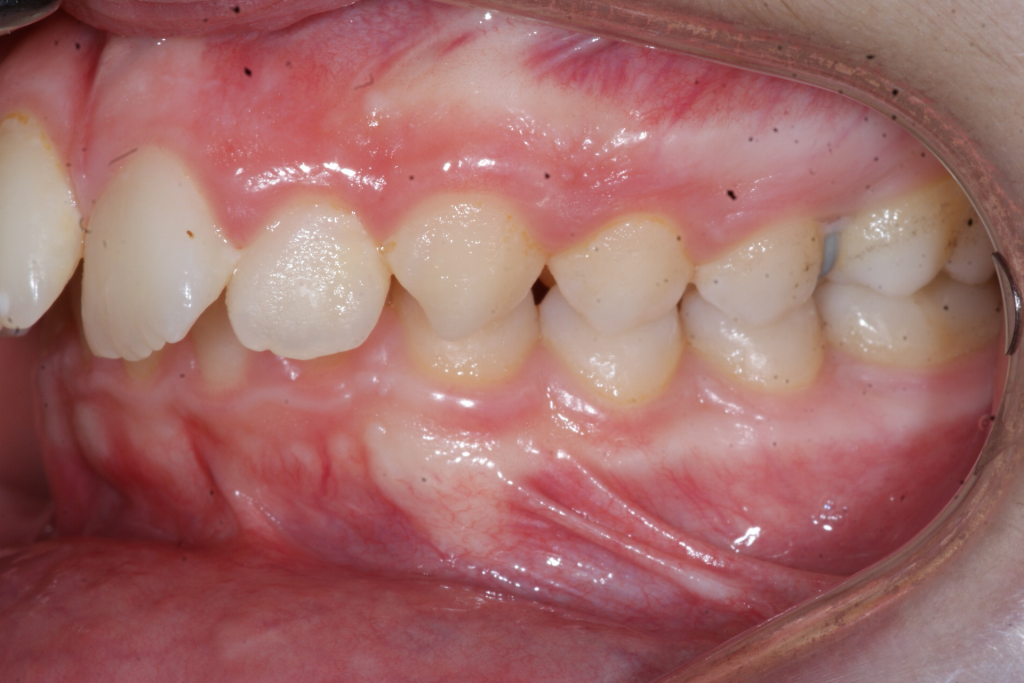

Correction d’une malocclusion de type Classe II.  Des appareils fixes (boîtiers) et une expansion palatine furent nécessaires pour améliorer ce sourire.  Traitement chez un adolescent, réalisé en 21 mois.